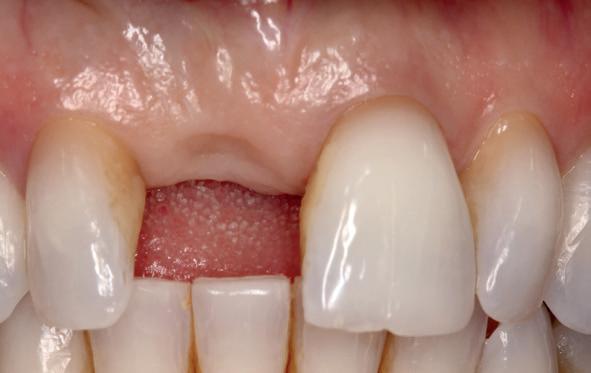

Implantologische behandelingen in het esthetische front vragen meer dan technische vaardigheid alleen. Ze vragen om overzicht, timing, vertrouwen en een team dat als vanzelf samenwerkt onder druk. Juist bij complexe casussen, waarin angst, infectie en hoge esthetische verwachtingen samenkomen, wordt zichtbaar hoe bepalend de rol van de tandartsassistent is.

Deze casus beschrijft een uitgebreide immediate implantaatbehandeling bij een patiënt die door meerdere collega’s werd geweigerd. Niet omdat de mogelijkheden ontbraken, maar omdat de complexiteit vroeg om een perfect afgestemde samenwerking. Het verhaal laat zien hoe de assistent in zo’n traject veel meer is dan een uitvoerende kracht of “mal”, maar een dynamische surgical guide die het proces mede stuurt, bewaakt en mogelijk maakt.De patiënt: wanneer alles samenkomt

Na het klinische onderzoek volgde het röntgenologisch traject. De CBCT liet precies zien wat we al vreesden: een front waarin het bot onregelmatig was, duidelijke radiolucenties rond de pijlers en een infectiegebied dat zich onder vrijwel de gehele brug had verspreid. Tegelijkertijd was er ook potentie. Net voldoende botstructuur om immediate implantaatplaatsing te overwegen, mits alles perfect gepland zou worden.

Twee weken later zie ik de patiënt terug voor controle van de eerste wondgenezing. De noodprothese mag de eerste twee weken niet gedragen worden en wordt tijdens de controle zorgvuldig aangepast aan de nieuwe situatie. Hiervoor wordt de prothese gedeeltelijk uitgefreesd en voorzien van een Soft Reliner materiaal. Te veel druk op de beide kaken moet ten alle tijden voorkomen worden en heeft effect op de ingroei van de botopbouw. De genezingsperiode duurt tenminste zes maanden voordat verdergegaan kan worden met de tweede fase: de abutment chirurgie. Hierbij wordt extra aandacht besteed aan het herstel van de gekeratiniseerde gingiva rondom de abutments. Dit komt ten goede aan de uitvoering van de mondhygiëne en dus de stabiliteit van de peri-implantaire mucosa. Deze ogenschijnlijk eenvoudige behandeling is essentieel voor de prognose van de implantaten op de lange termijn. Te weinig gekeratiniseerde mucosa maakt zelfzorg (borstelen/interdentaal reinigen) vaker pijnlijk of lastig, waardoor plaque en mucositis makkelijker kunnen ontstaan en blijven over de lange termijn. Dat kan bij patiënten die vatbaar zijn voor peri-implantitis zich vertalen naar crestaal botverlies rondom implantaten. Gek genoeg wordt de essentie van het herstellen van de gekeratiniseerde gingiva rondom implantaten regelmatig genegeerd.

Herstel van gekeratiniseerde mucosa en weke delenmanagement

De breedte en kwaliteit van de peri-implantaire mucosa beïnvloeden niet alleen esthetiek, maar met name de uitvoerbaarheid van zelfzorg en de stabiliteit van de mucosale barrière. Consensus reports en meta-analyses laten zien dat een beperkte of afwezige col van gekeratiniseerde peri-implantaire mucosa (vaak gedefinieerd als <2 mm) geassocieerd kan zijn met (1) meer plaque-accumulatie, (2) meer wekedelen-inflammatie, (3) meer mucosale recessie, (4) meer marginaal botverlies en (5) een hogere prevalentie van peri-implantitis.4-6 In de dagelijkse praktijk is dit vooral relevant bij full-arch restauraties waarbij de connectie prothese-abutments en de overgang prothese-mucosa moeilijker te reinigen zijn. Bij onvoldoende gekeratiniseerde mucosa of een ondiepe omslagplooi wordt poetsen vaak pijnlijk, waardoor plaquecontrole onvoldoende is en peri-mucositis gemakkelijk ontstaat. Dit verdedigt de indicatie voor een wekedelen augmentatie als chirurgisch onderdeel van de implantologische behandeling. Streefwaarde van ongeveer ≥2 mm gekeratiniseerde mucosa rondom implantaten wordt in de literatuur vaak gehanteerd.4, 5 Technisch kan dit in de tweede fase (abutmentchirurgie) voorafgaand aan de prothetiek worden uitgevoerd met een apicaal gepositioneerde flap, al dan niet gecombineerd met een gesteelde dan wel een vrij bindweefseltransplantaat (free gingival graft, FGG). FGG geldt als ‘standard of care’ voor voorspelbare toename van gekeratiniseerde mucosa. Xenogene collageenmatrixen kunnen in geselecteerde gevallen een alternatief zijn, bijvoorbeeld om donor site morbiditeit te beperken.4 Waar dikte en contour belangrijk zijn (recessies/esthetiek) wordt vaker een bindweefseltransplantaat overwogen.